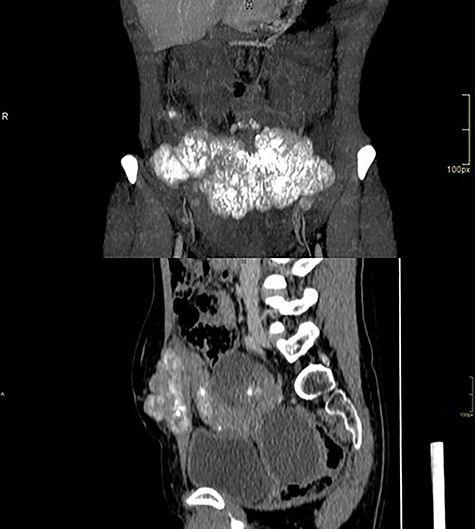

Computed tomography of the abdomen showed solid-cystic lesions in the pelvis (Fig. 2) and a massive expansive lesion in the AW, with soft tissue density and a volume of 334 cm3 (Fig. 3). Between the AW and the pelvic lesions, formation with soft tissue density, heterogeneous enhancement and calcifications are identified, measuring 12.5 × 2.5 cm in the major latero-lateral and anteroposterior axes, compatible with ‘omental cake’.

Abdominal wall CT with expansive lesion with soft tissue density, heterogeneous, with the appearance of a cluster of nodules, measuring 16.4 × 5.1 × 7.7 cm (334 cm3 volume) in the major latero-lateral, antero-posterior axes and longitudinal, respectively.